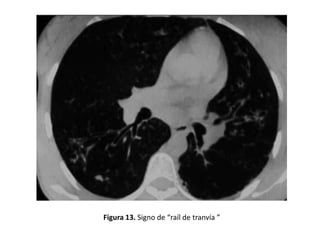

• En el caso de que el bronquio transcurra paralelo al

plano de sección, la dilatación anormal se reconoce por

la falta del progresivo afilamiento bronquial

– Ausencia de reducción del calibre bronquial desde la

división dicotómica. (Figura 12)

• Pueden visualizarse asimismo bronquios dilatados

dando lugar al signo del "raíl de tranvía". (Figura 13)

Figura 13. Signo de “raíl de tranvía ”